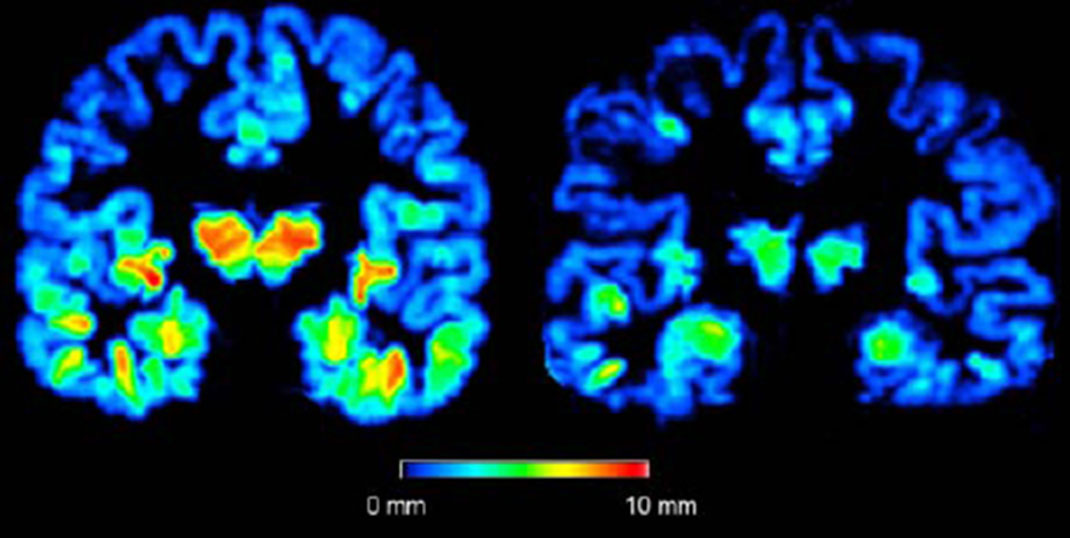

Rétrécissement cérébral

Une étude scientifique a démontré que les adultes en bonne santé mais qui manquent de sommeil perdent du volume dans le lobe frontal, pariétal et temporal. Cependant les scientifiques n’ont pas encore déterminé si c’est le manque de sommeil qui est responsable du rétrécissement ou si c’est le rétrécissement qui induit des insomnies.